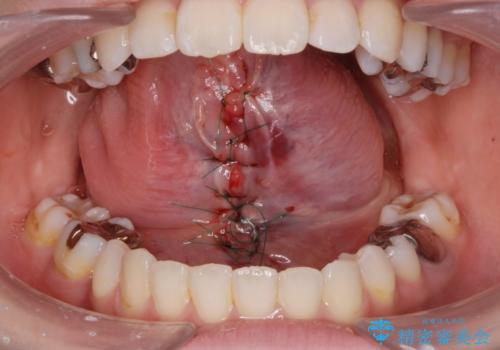

- 舌が動かしにくく、過去に舌小帯切除を行ったがあまり切除されず後戻りをしたため、舌小帯切除を希望されました。

舌小帯の形成術を行い、舌の可動域を広げました。